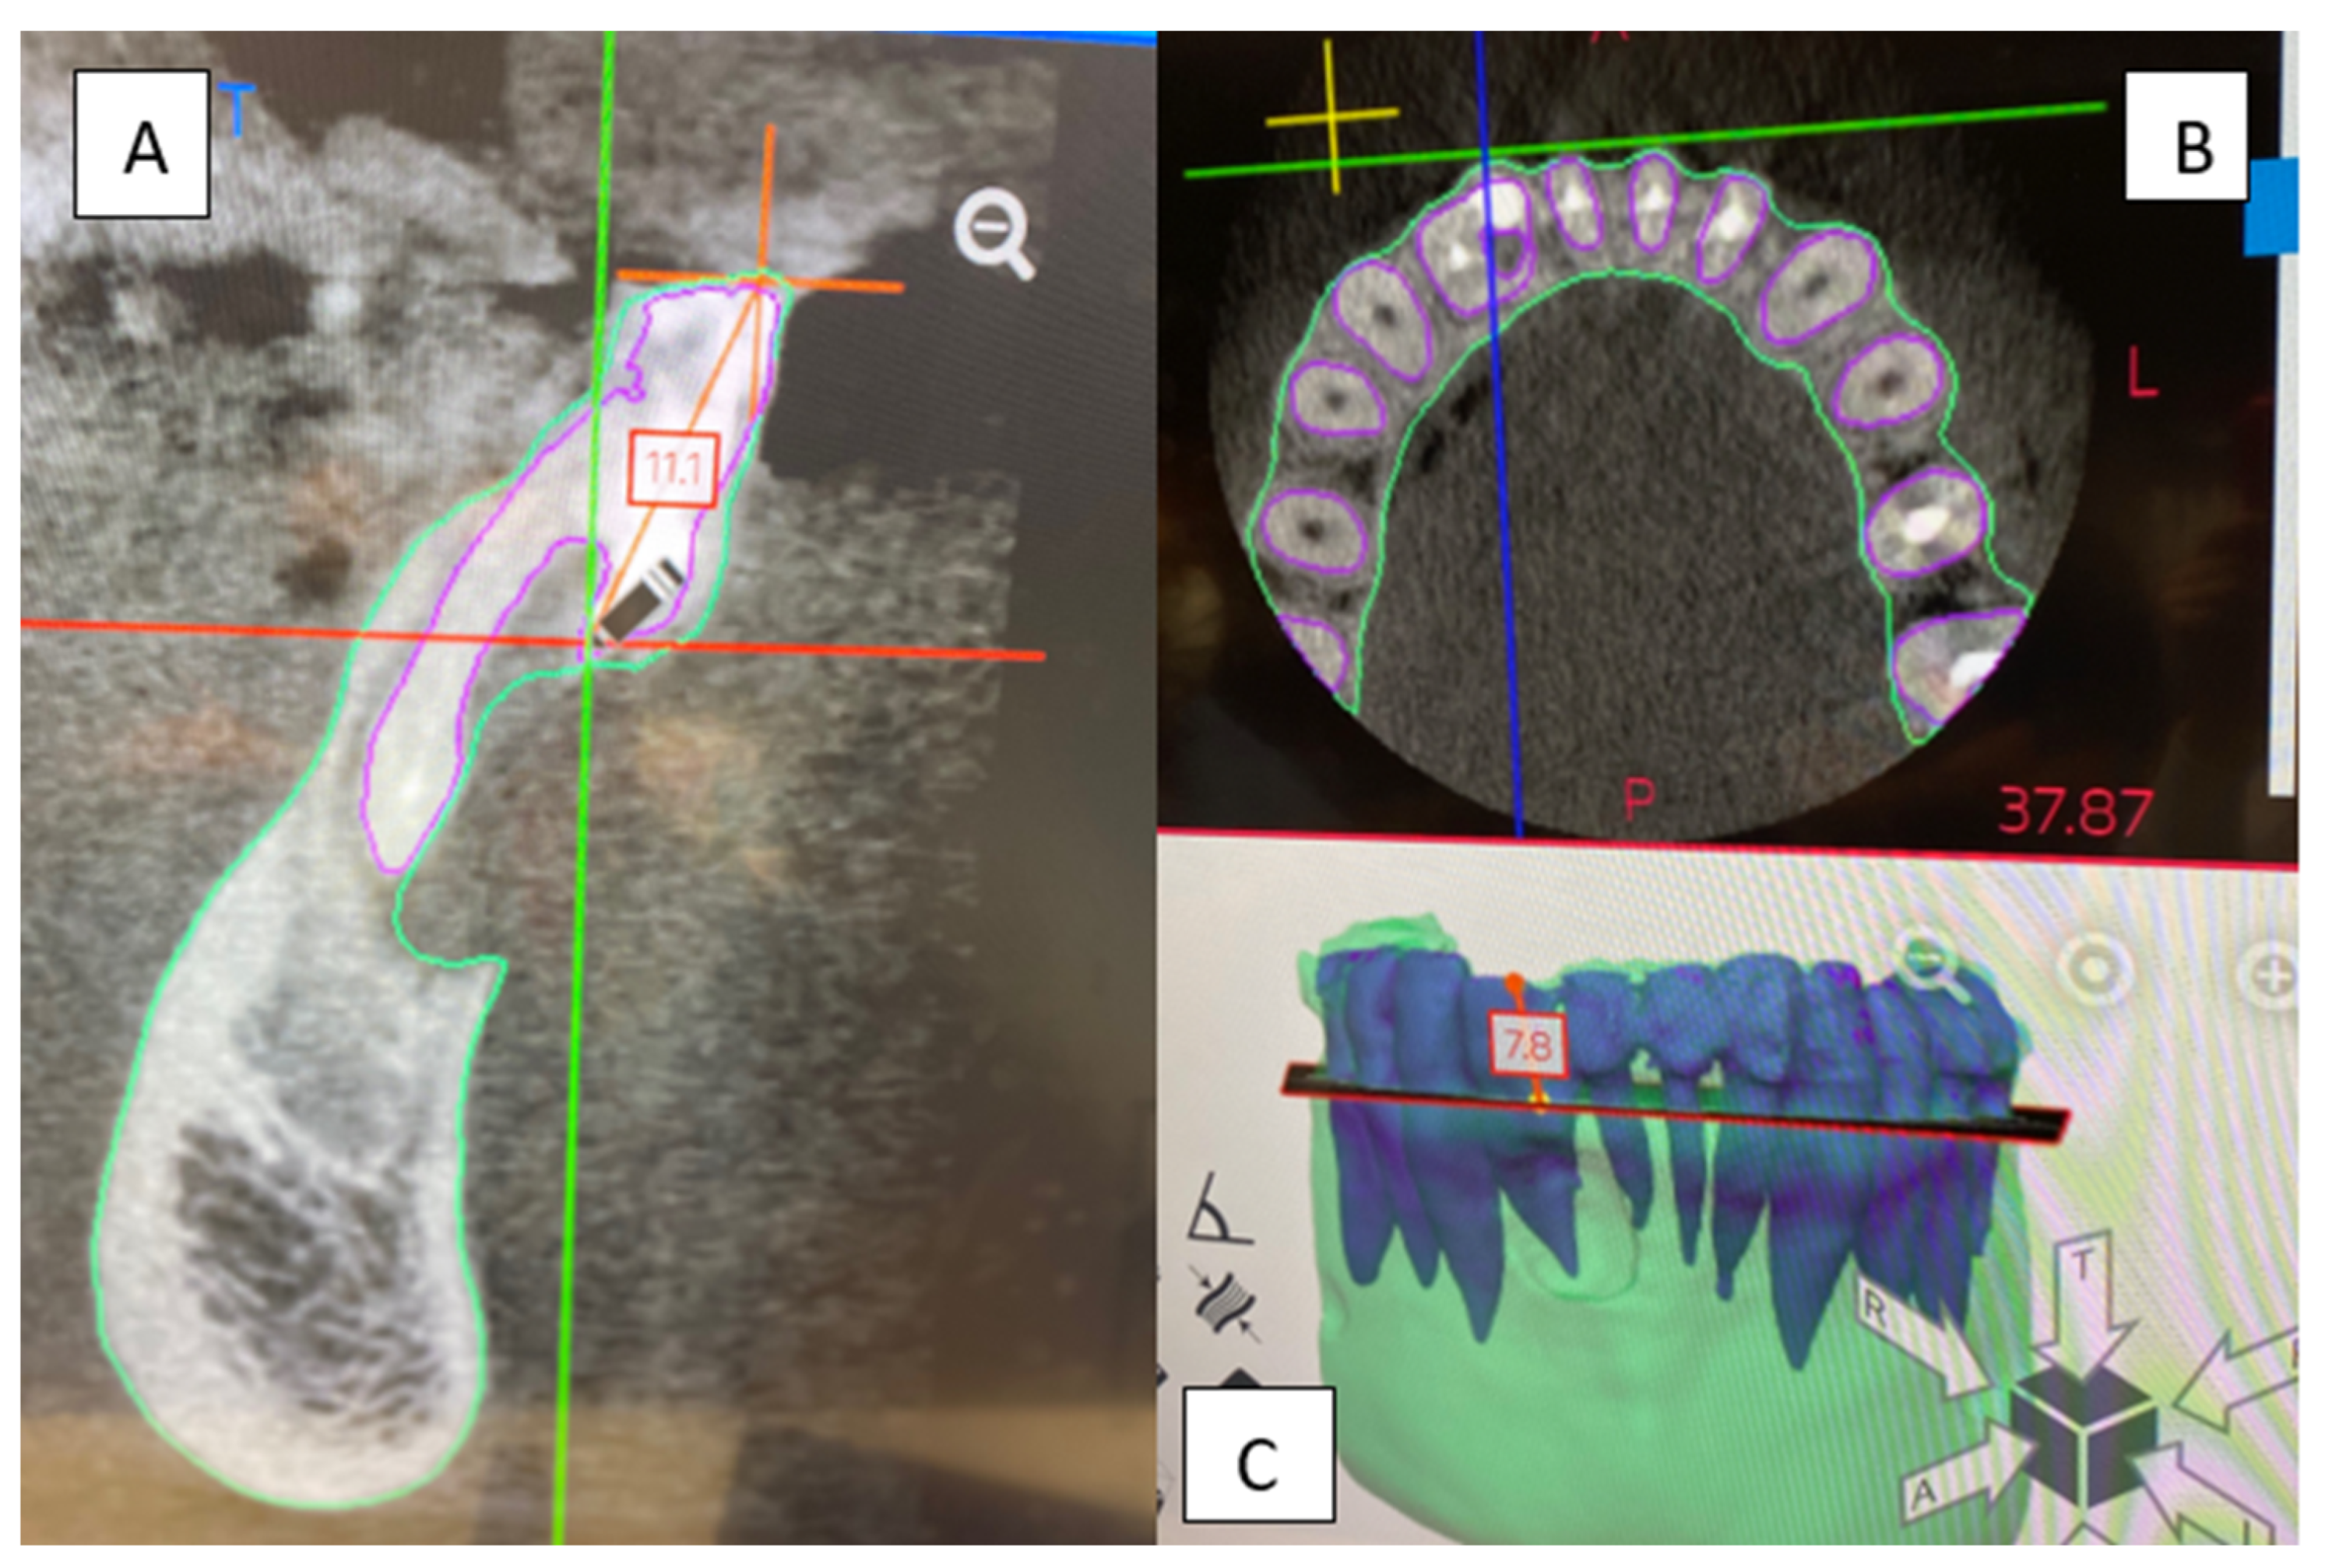

A 32-year-old female was referred to the Graduate Endodontic Clinic at the University of Detroit Mercy School of Dentistry for evaluation and treatment of a mandibular right lateral incisor. The patient’s health history was noncontributory. Extraoral examination was unremarkable. Intraoral examination revealed a fixed prosthesis from #23–#24 and a metal–ceramic crown on #25. Tooth #26 was wider in a mesiodistal dimension relative to the adjacent crowns. There was a mesial composite restoration. There was no pain to percussion or palpation, no mobility, no response to cold or electric pulp testing, and periodontal probing was 2–3 mm circumferentially. Periapical radiographs showed two canal spaces. The main distal canal had a normal shape with a completely formed root apex. The mesial invaginated portion was consistent with a rare type of DI Type IIIa. The invagination had a wide opening extending obliquely along more than half the length on the mesial wall of the distal root (Figure 1). There was a periapical lesion involving #26 and #25. Dimensions of the lesion on CBCT measured 25.2 × 15 × 12.4 mm. The endodontic diagnosis was pulpal necrosis with asymptomatic apical periodontitis. Due to the extensive nature of the periapical pathology, the patient was seen previously by an oral surgeon for biopsy 11 months prior to the endodontic evaluation. The specimen was most consistent with an inflammatory cyst. Based upon the DI complexity, further analysis was needed for a clearer understanding of the morphology. A digital rendering was utilized for measurements of critical structures and to plan the creation of 3D models (Figure 2 and Figure 3). Two 3D models were produced from Materialise (Plymouth, MI, USA). The first 3D model replicated the tooth itself and the second model exhibited the location and orientation of the tooth within the alveolus (Figure 4). The software packages used were Materialise Mimics Medical 23.0 (Materialise NV, Leuven, Belgium) and Materialise 3-matic Medical 15.0 (Materialise NV, Leuven, Belgium). At the crestal bone level, the canal turned distally at a 45-degree angle, opened widely along the adjacent root surface, and continued as part of the major foramen. The complex morphology of the DI foramen opening was bordered by three major anatomical dentinal structures: a mesiofacial projection, a lingual wing forming most of the invaginated structure, and the main axial root surface of the distal root. The lingual wing of the root in the coronal plane extended beyond the DI foramen nearly to the level of 2 mm from the root apex (Figure 4 and Figure 5). The wing terminated at a subtle notch apically. The mesiofacial projection acted as a partition extending 5 mm in the apical direction from the most coronal portion of the apical opening. The 3D model allowed us to see a subtle depression nearly to length in the axial root surface. The arrangement of these structures resembled a half-tube formation with a very wide opening.

Figure 2. Renderings used during the design process. (A,C) Teeth #25–#27 within the alveolus. Both the DI and the lesion are modeled. (B) Teeth #25–#27 with overlaid axial and coronal CBCT sections. (D) CBCT imaging used to design 3D tooth model with mapping of the DI and surrounding tissues.

Figure 3. CBCT sagittal (A) and axial (B) sections of tooth #26. (C) Measurements taken from the CBCT sections and 3D software aided in accurate non-surgical and surgical planning. Axial section apically showing dilated space of DI.

Endodontic success depends on proper case selection, accurate diagnosis, and precise treatment planning [21,22]. The treatment outcome of teeth with DI, especially those associated with apical periodontitis, involves a more comprehensive approach to achieving adequate disinfection and sealing quality. The use of the CBCT and the production of 3D models contributed significantly to our understanding of the 3D nature of the complex morphology of DI, the surrounding tissue defect, and proper treatment management. The use of the two 3D models at the pretreatment planning stage were of great value to determining the necessary treatment protocol for nonsurgical treatment of the main distal canal and surgical treatment for the DI. The use of 3D printed models from CBCT for endodontic teaching purposes has previously been described [23]. With the unique challenges associated with this rare and complex DI Type IIIa identified before treatment, the treatment team prepared the patient properly for the selected treatment strategy. All underlying structures were known and planned for accordingly. The procedure was executed efficiently and led to healing without incident. The 3D model accurately simulated the clinical presentation upon flap reflection and access to the surgical area (Figure 5). It is worth noting that achieving this kind of accuracy depended on coordination with the software engineer. The engineer works on detail to the level of the voxel in the designing process. Careful interpretation of the CBCT between the endodontist and the software engineer is essential to creating a 3D model that provides the maximum benefit to presurgical planning and to facilitate the surgical procedure itself (Figure 2, Figure 3, Figure 4 and Figure 5). The use of tooth models has been profiled in a case report supporting the use of 3D models to address an anomalous complex anatomy [24] and improve workflow and add objectivity to the treatment planning process [25].